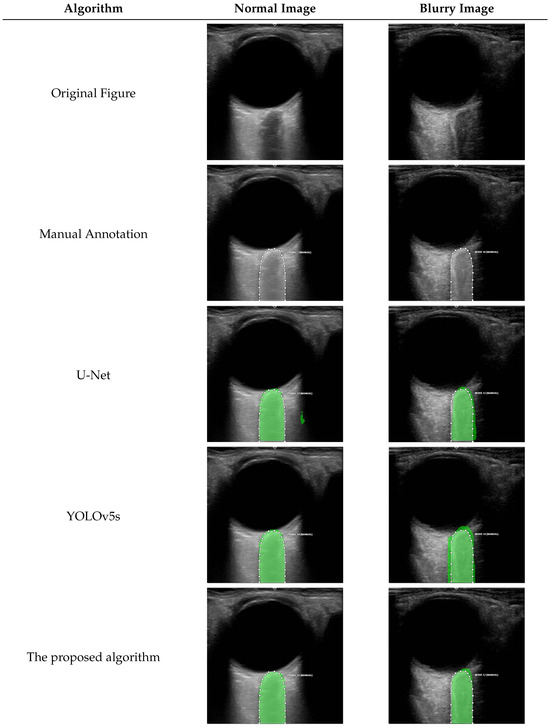

3.4.2. Specific Segmentation Example

As shown in Figure 6, compared to the manual annotations by the operators, for the normal image with a clear optic nerve sheath boundary, the U-Net [11] network makes some segmentation errors due to over-focusing on the other regions. In contrast, YOLOv5s and the proposed algorithm focus more accurately on the optic nerve sheath area, resulting in more precise segmentation. For the blurry image, due to the blurry optic nerve sheath boundary, both the U-Net [11] and YOLOv5s networks, limited by their local receptive fields, exhibit significant segmentation errors. However, the proposed algorithm achieves a closer match to the true annotation by capturing the global information of the optic nerve sheath.

Figure 6.

Different algorithms for segmentation examples with normal and blurry images.